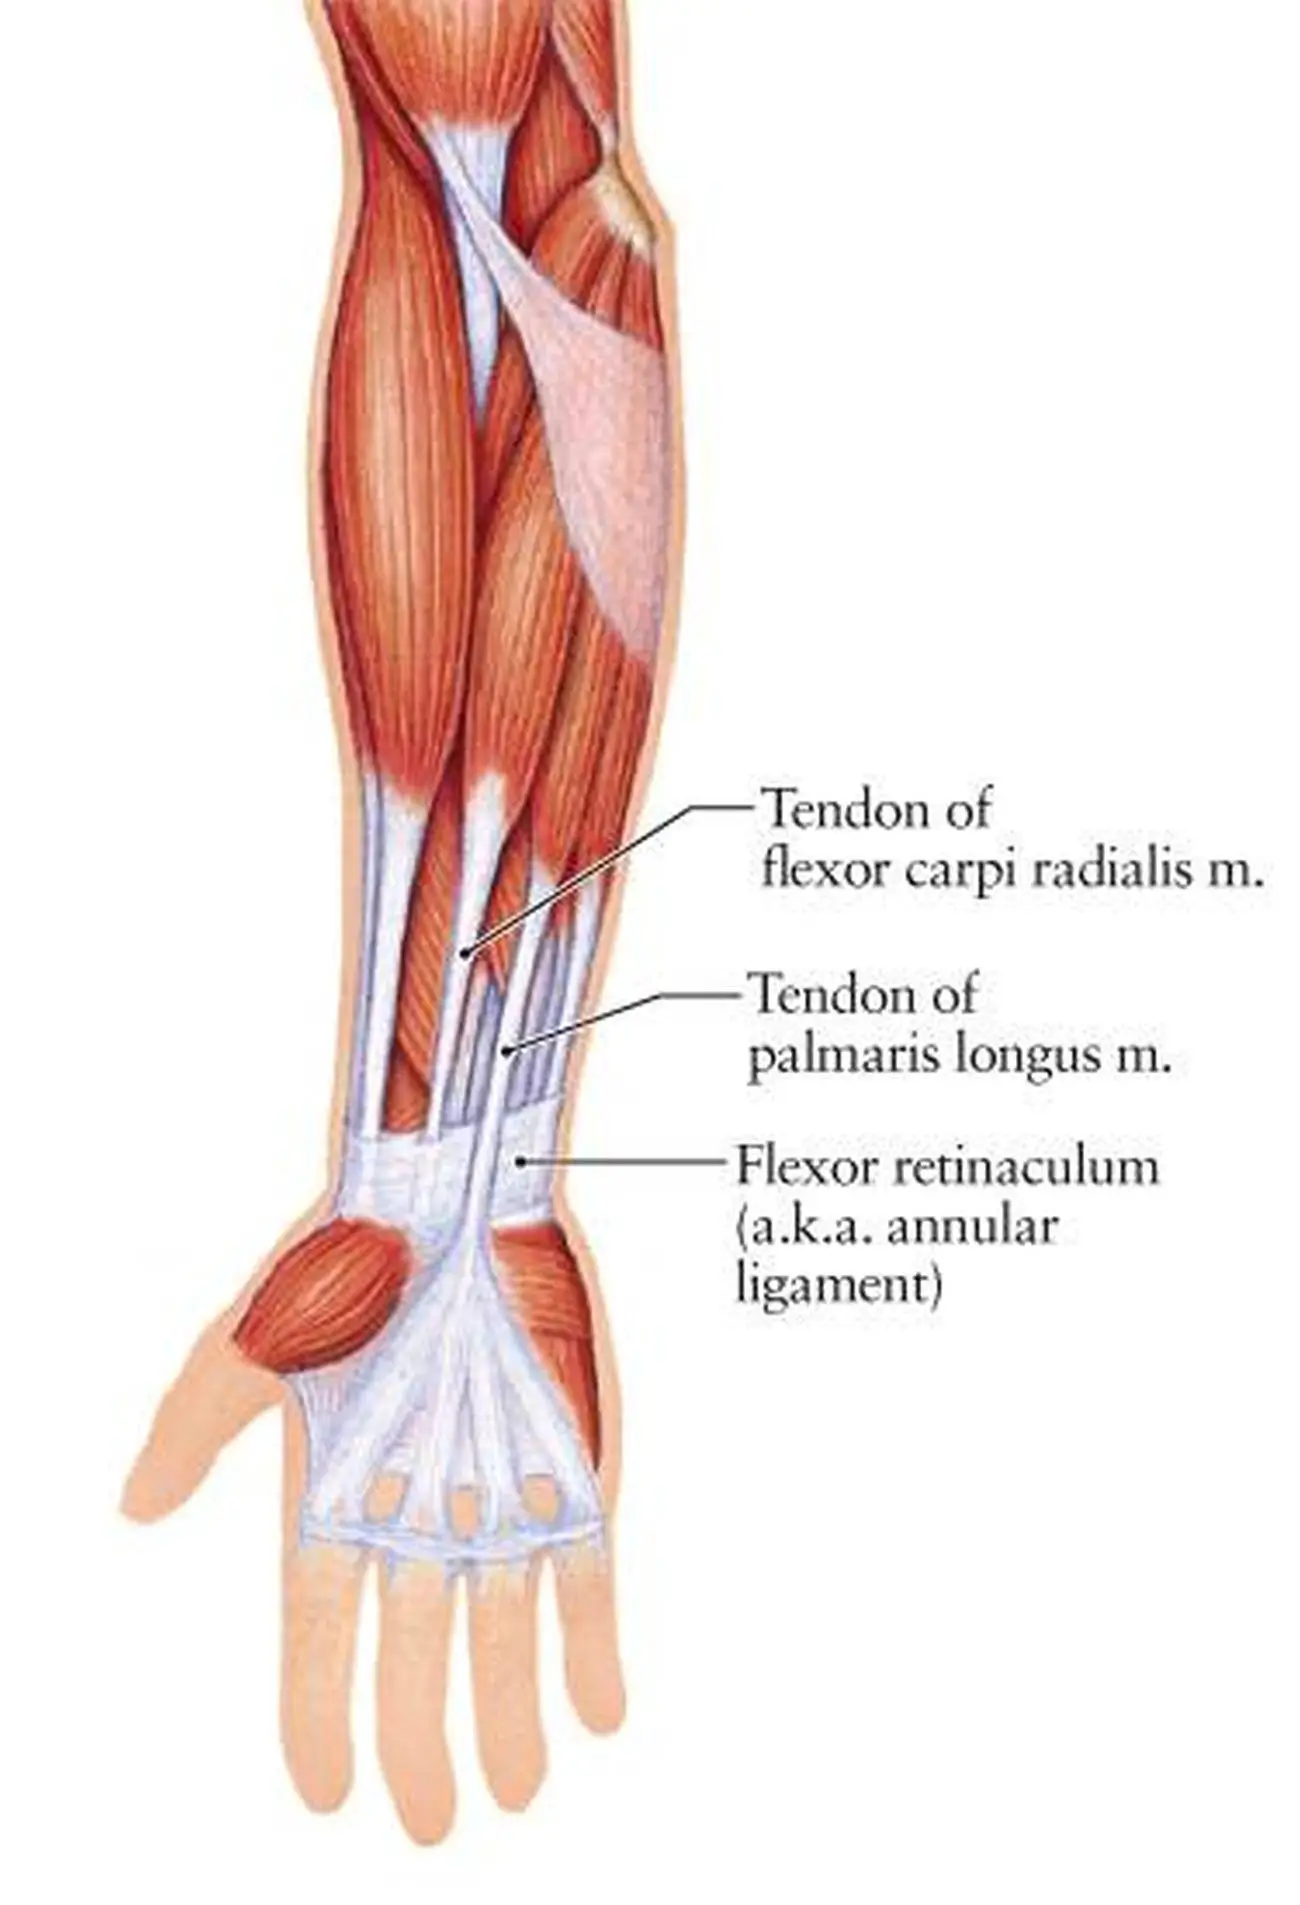

Анатомия мышцы Palmaris Longus